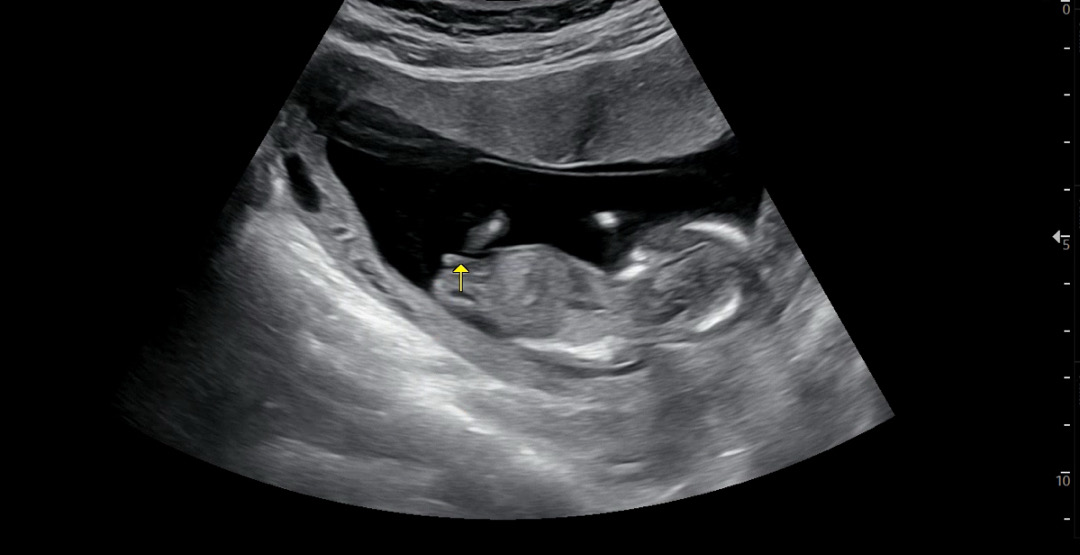

각도법 봐주실분 계실까용 의사쌤은 확실해지면 얘기해주신다고해서,, 12주 6일입니당